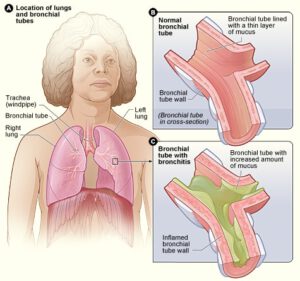

Bronchiolitis and Respiratory Syncytial Virus (RSV)

Cheatsheets

1

Mnemonics

0

Images

1

Picmonic

0